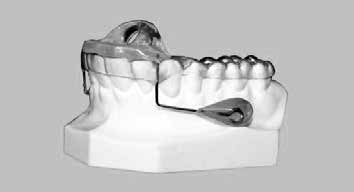

- Decompression appliance therapy, see Figure 10, (night orthotic that prevents mandibular retrusion, reduces clenching forces and opens nasal valve), for cant correction and leveling of the occlusal plane utilizing the phonetic or sibilant phoneme registration [20] and reducing of oropharyngeal airway collapse while sleeping with combined use of weekly treatments with a dual wavelength, high power IR laser (Multiwave Loked System (MLS®) laser, Mphi, ASA srl, Vicenza, Italy) see Figure 11, using the following treatment parameters: 50% intensity, frequency of 100 Hz, for 2-3 minutes utilizing energy of 30 joules and carbamazepine 100 mg four times per day. Treatment time 10-12 weeks and re-evaluation.